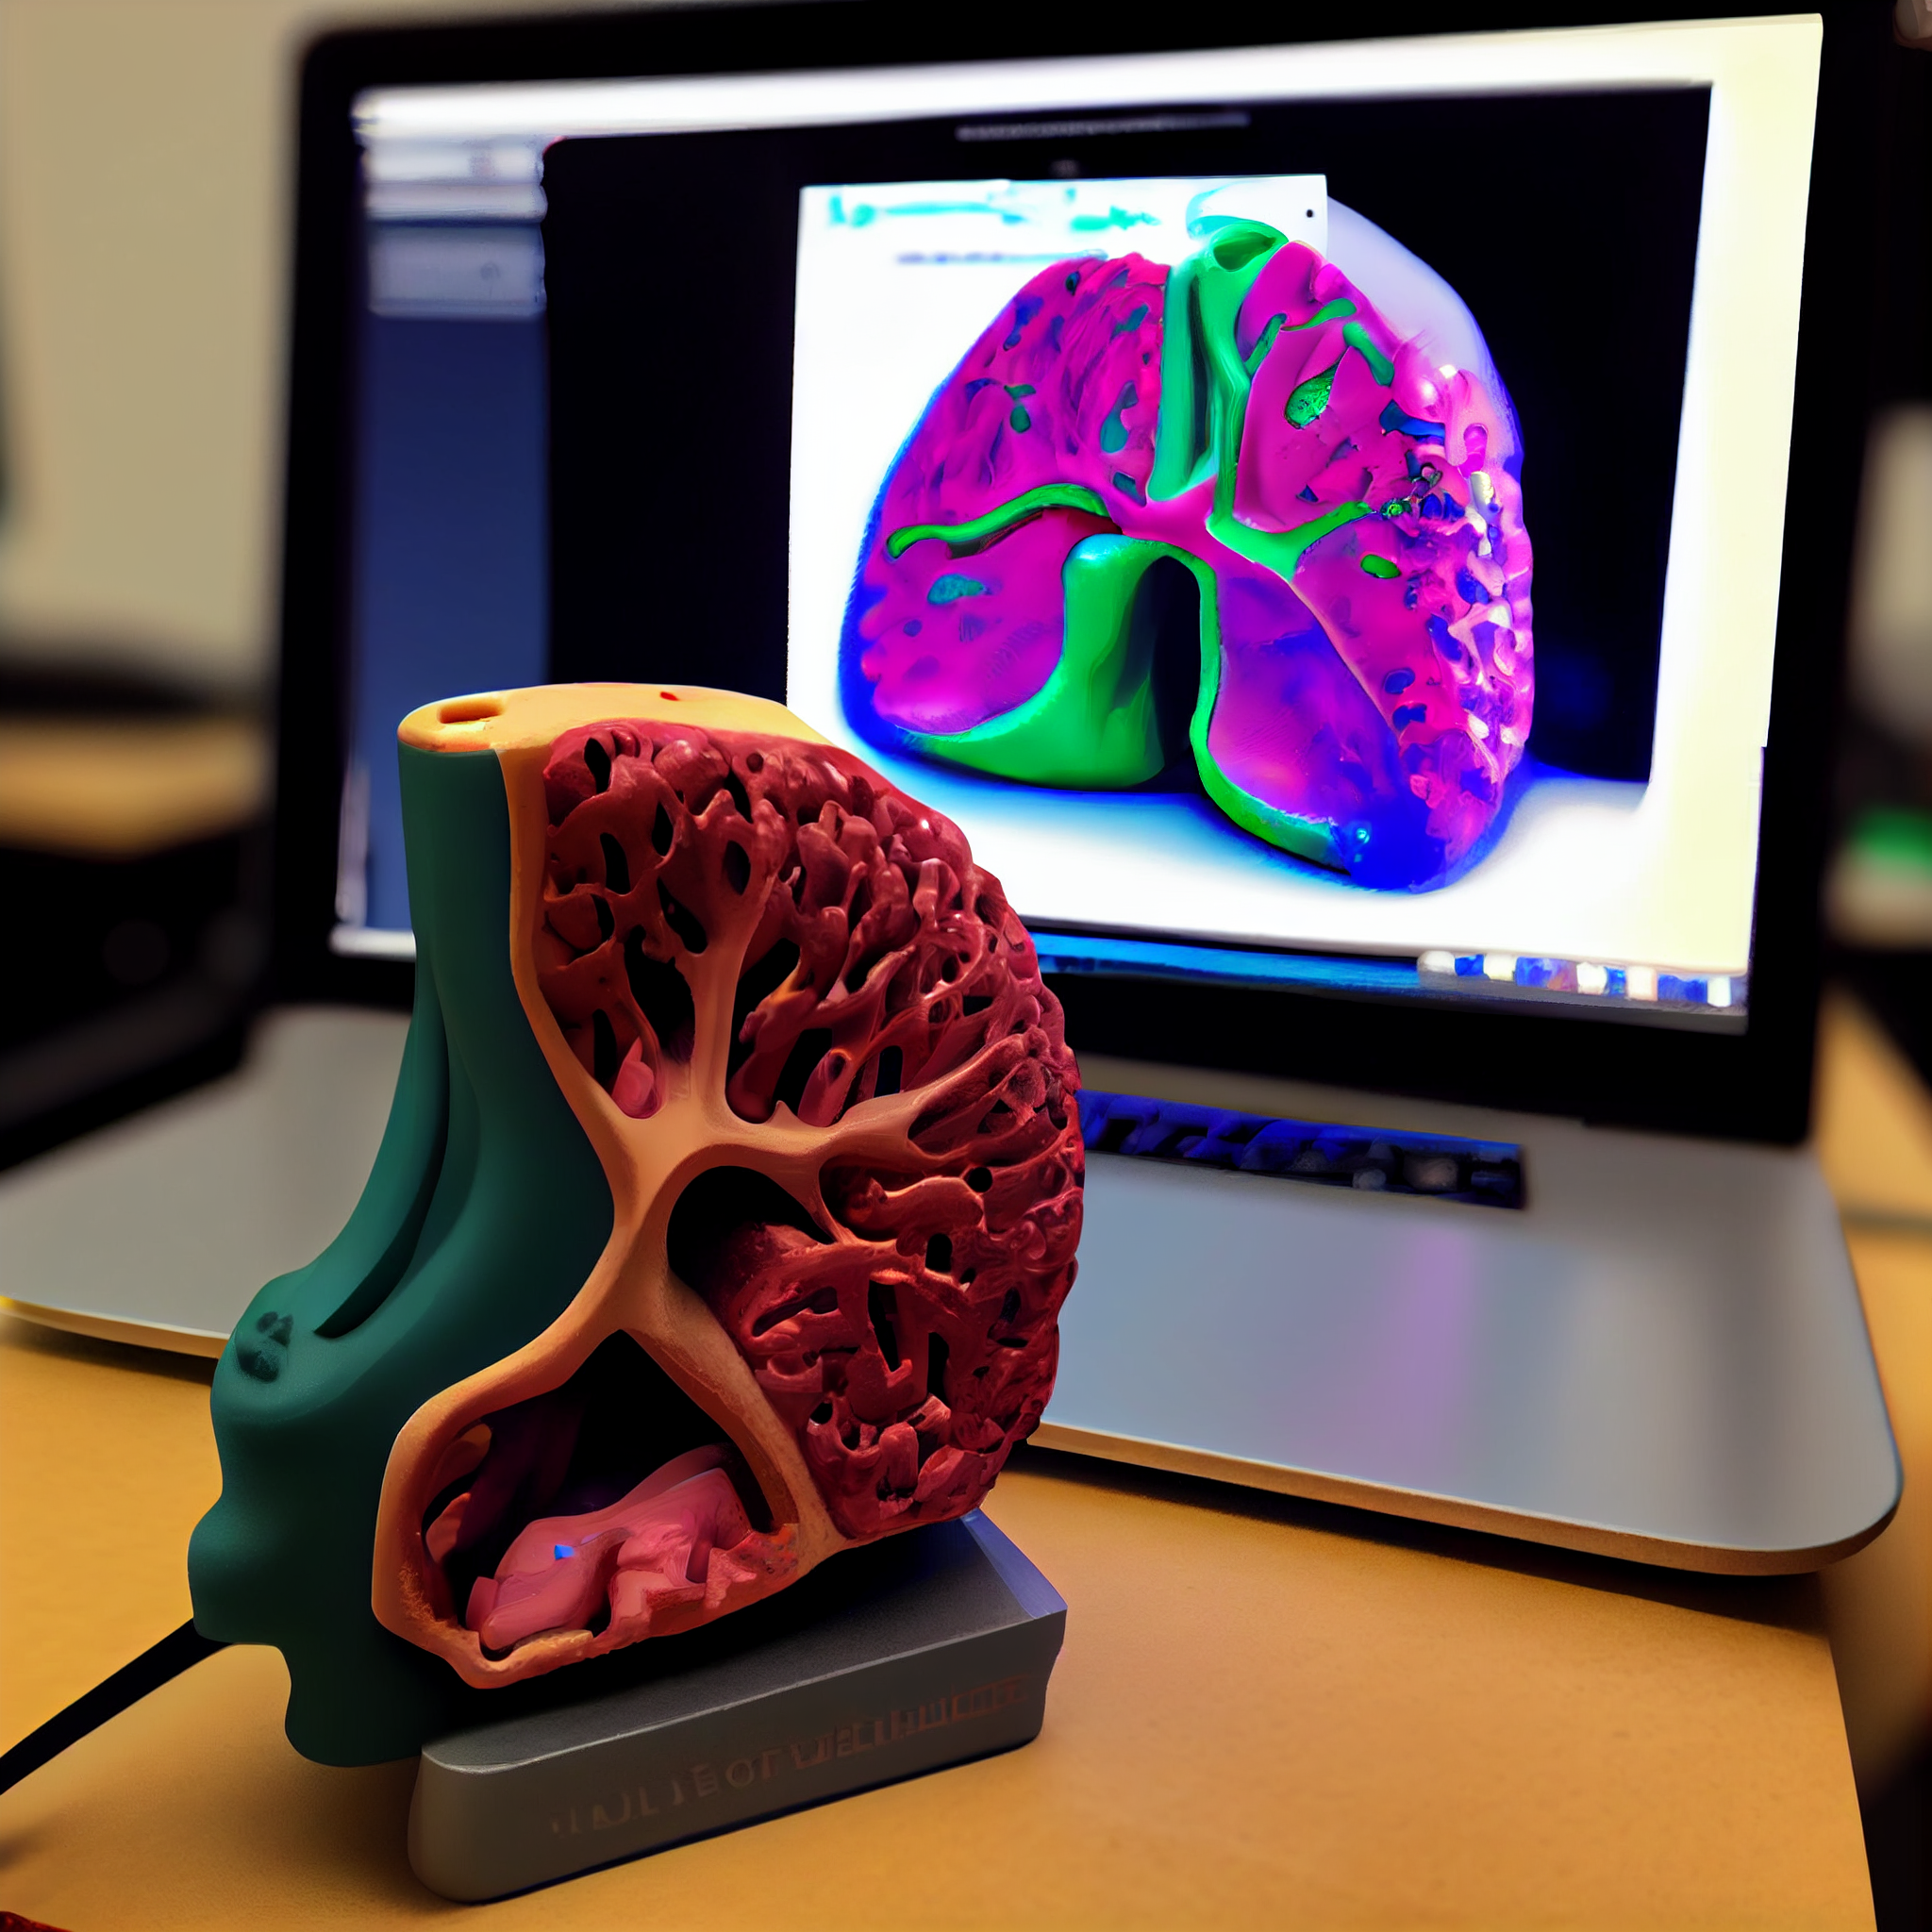

Experience the benefits of 3D printing in surgery with a personalized 3D printed model tailored to the patient's needs, assisting surgeons in achieving the best possible outcome for the surgery.

3D printing has revolutionized pre-surgical planning by providing doctors with accurate and detailed 3D models of patient anatomy. With 3D printing technology, doctors can now visualize complex structures and plan surgical procedures with greater accuracy and precision. This technology enables doctors to identify potential risks, explore different surgical options, and develop personalized treatment plans for each patient. 3D printing also helps to reduce surgery time and minimize the risk of complications, resulting in improved patient outcomes. With 3D printing, doctors can enhance their pre-surgical planning process, delivering better care to their patients.

While performing a surgical procedure, the stakes are high, and even a small error can have disastrous consequences. Therefore, it's crucial to be well-prepared for any unexpected challenges that may arise during the surgery. By taking the necessary precautions and having a detailed plan of action, surgeons can ensure the best possible outcome for their patients. In the world of life and death, preparedness is the key to success.

Our state-of-the-art surgical preparation service includes the use of advanced technology such as

3D printing to provide surgeons with accurate and detailed anatomical models. By using patient-specific

CT and MRI scans to create these models, surgeons can perform mock surgeries to plan and prepare for the

actual procedure. This process not only helps to avoid any potential surprises during surgery but also

boosts the surgeon's confidence and morale, knowing they have a comprehensive understanding of the

patient's anatomy. With our advanced preparation techniques, you can rest assured that your surgical

team is fully equipped to provide you with the best possible outcome.

Transforming surgical planning with customized 3D printed models, created from patient CT and MRI scans. Our cutting-edge 3D printing technologies, including FDM, SLS, and SLA, allow for precise and accurate replicas that provide invaluable preoperative and operative guidance for surgical teams. In addition, we provide virtual 3D models in multiple file formats, enabling further analysis and planning for optimal patient outcomes. Trust us to enhance your surgical precision and improve patient care with our advanced 3D printing solutions.

Revolutionize surgical precision with personalized 3D printed surgical guides, designed to minimize the risk of errors and ensure optimal accuracy. Our state-of-the-art 3D printing technologies, including FDM, SLS, and SLA, allow us to create customized surgical guides that fit each patient's unique anatomy and aid surgeons in achieving unparalleled precision, even in the absence of unexpected elements. Trust us to provide cutting-edge solutions that enhance your surgical outcomes and improve patient care.

Revolutionize surgical planning with real-time 3D virtual models, generated from patient CT and MRI scans. Our cutting-edge technology allows for visualization of the patient's case in real-time, providing invaluable insights for preoperative surgical planning. These 3D digital models can be exported in various file formats, enabling numerous applications for further analysis and planning. By improving the comfort and efficiency of your doctor/surgeon to comprehend and operate, our virtual 3D models enhance surgical precision and patient outcomes. Trust us to deliver innovative solutions that transform the way you approach surgery.